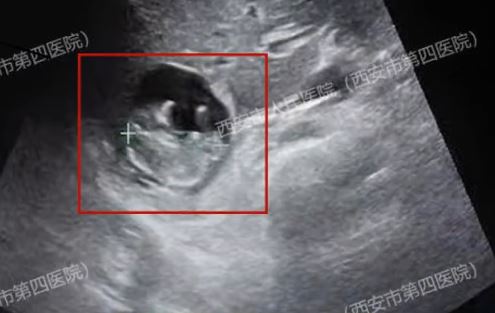

起點新聞報道,40歲王女士停經50天,於是接受抽血檢查,發現自己已經懷孕,不過,離奇的是,醫生用超聲波檢查卻遍尋不獲孕囊,以為是檢查「擺了烏龍」。

不過,王女士之後到了西安市人民醫院(市四院)再做檢查,醫生發現她的胎兒,原來寄生在肝臟,是極為罕見的「肝臟妊娠」。